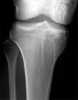

Osteopathia striata